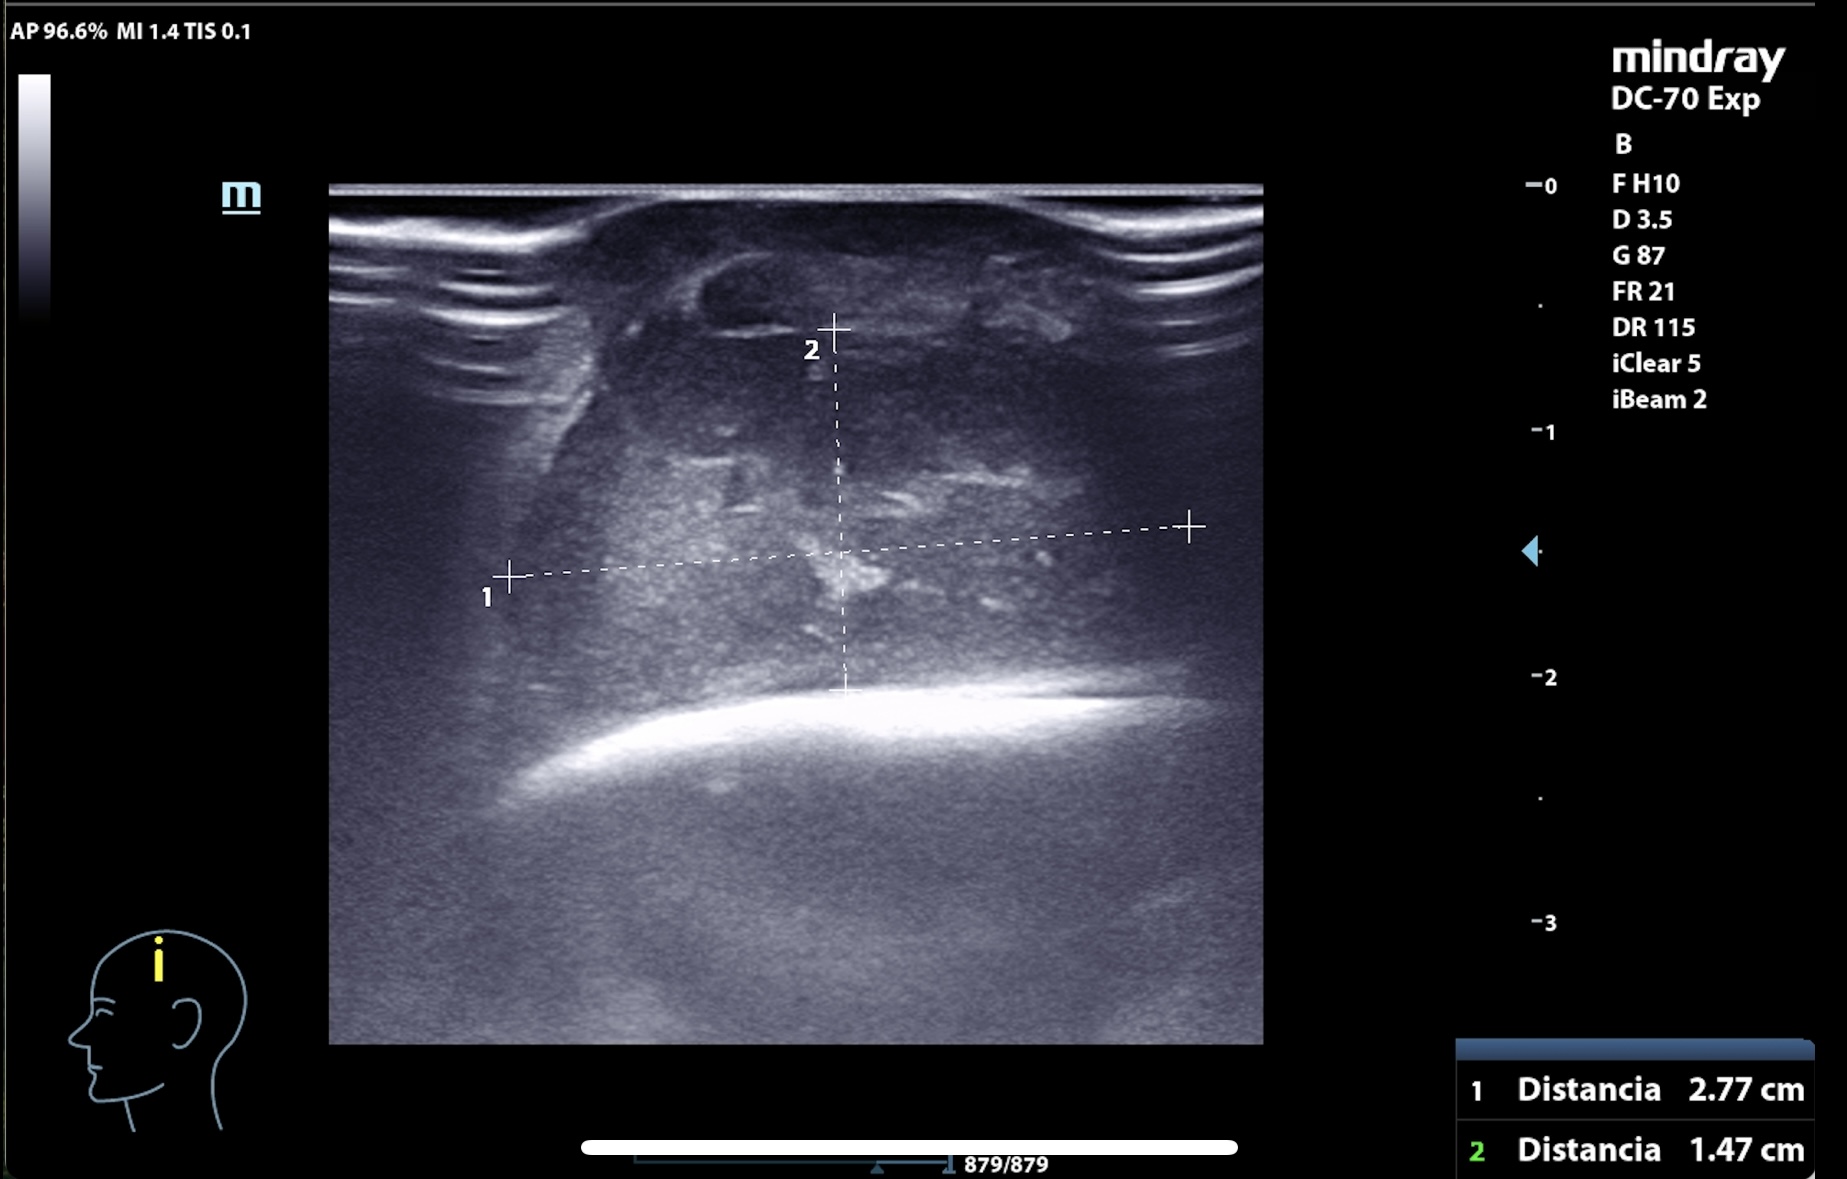

Se realiza en consulta ecografía, donde, para evitar la contaminación, se utiliza una funda estéril con gel conductor en su interior y clorhexidina entre la sonda y el cuero cabelludo como conductor líquido.

La imagen muestra una lesión heterogénea, con bordes netos, pero sin cápsula, microcalcificaciones en su interior y zonas hipoanecogénicas de necrosis líquida interna, así como vascularización interna intensa en Doppler. El patrón sugería proceso infiltrativo, por lo que se priorizó derivación urgente a dermatología.